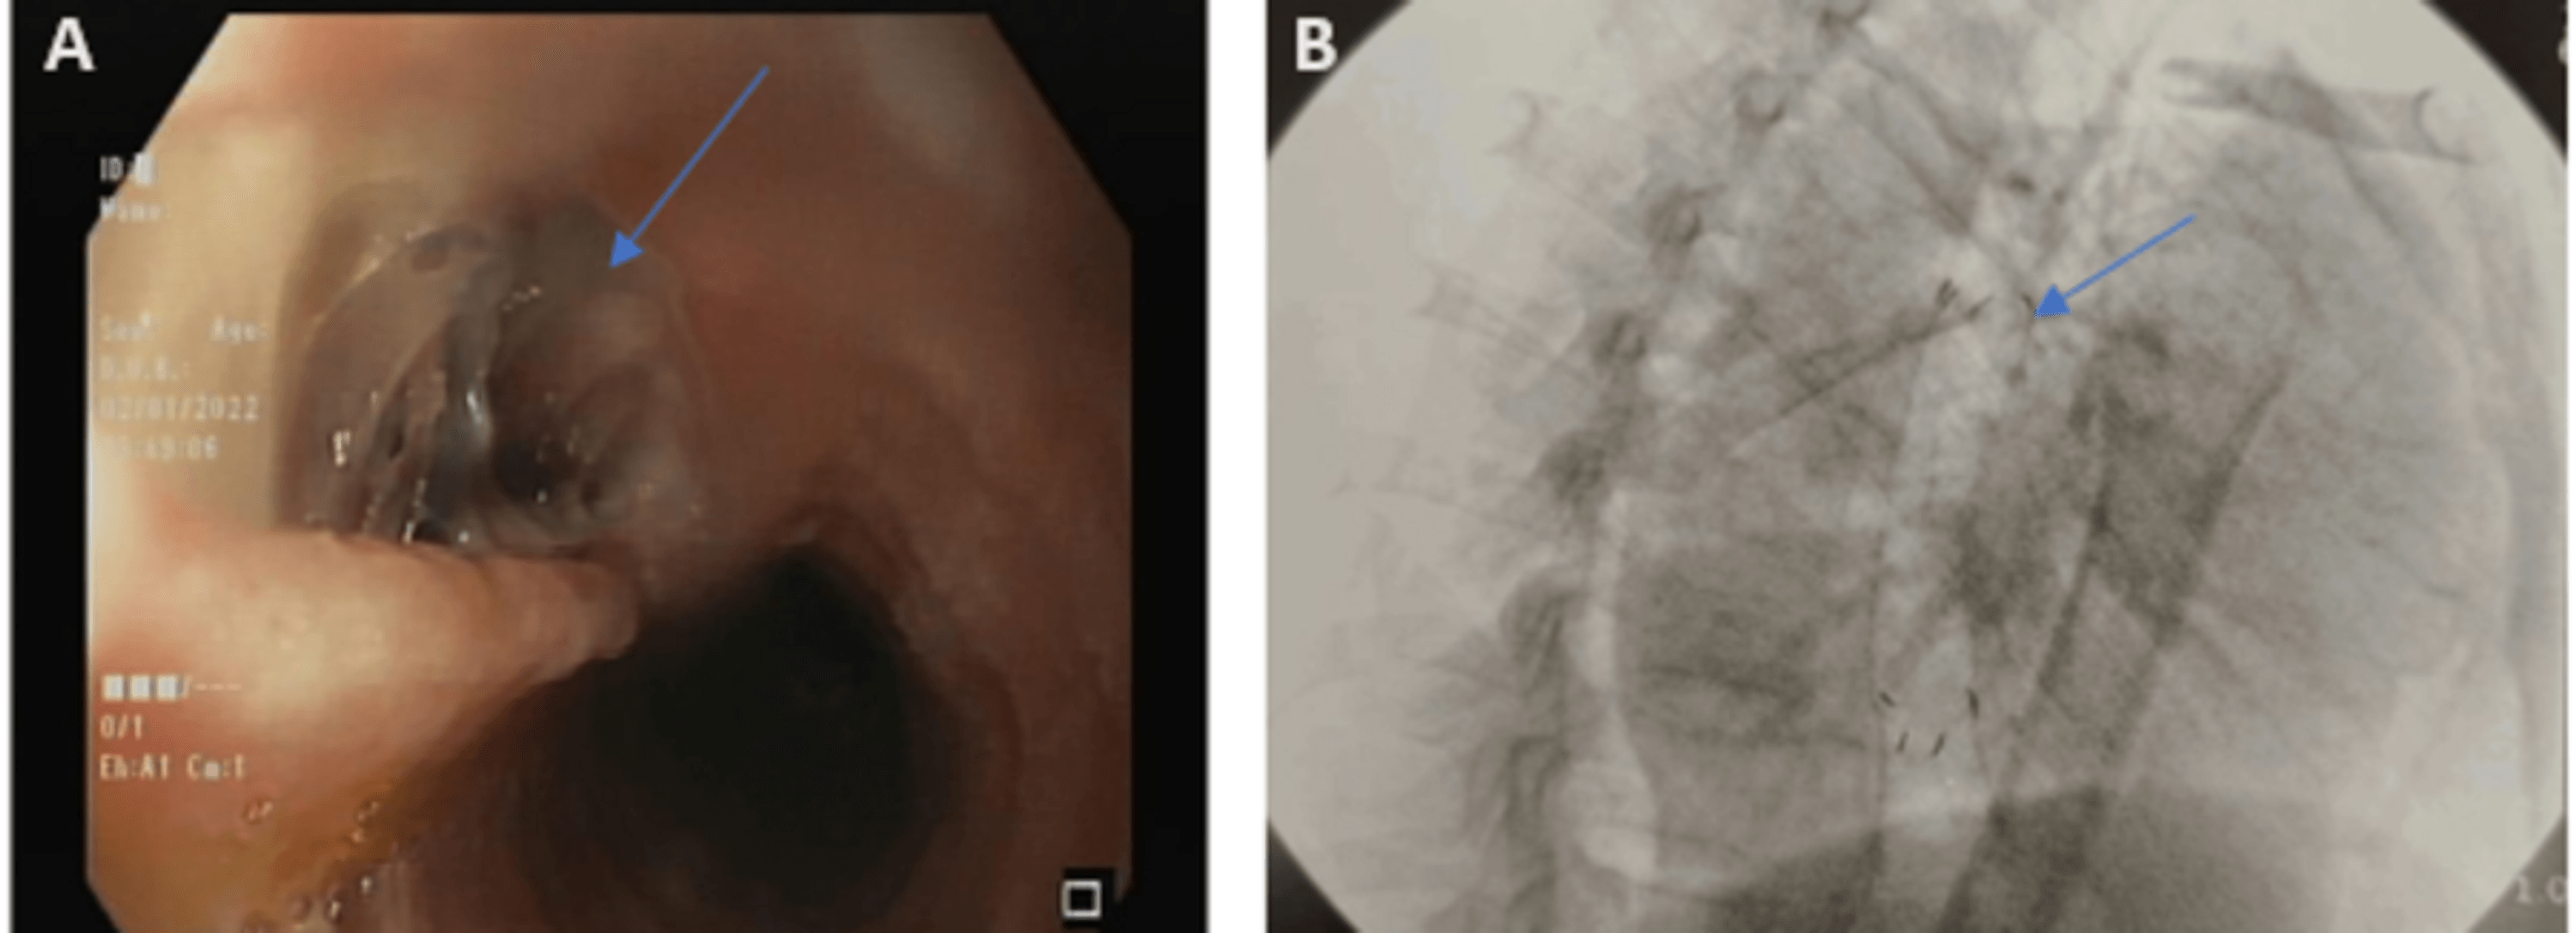

Figure 3 from A Case of Fishboneinduced Esophageal Perforation Closed Endoscopic Clipping Esophageal Perforation Recognizing iatrogenic perforations immediately during endoscopy. With advances in endoscopic technologies, endoscopic clips have been used. Recognition of significant bowel wall injury and perforations during endoscopy prevents the delayed diagnosis of. Although surgical closure has traditionally been the gold standard care for patients with esophageal perforation, there is an emerging. Endoscopic Clipping Esophageal Perforation.